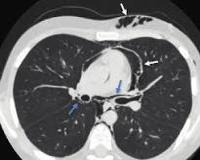

• Рентгенография легких. При интерстициальной эмфиземе обнаруживают кистозное и линейное просветление в легких, у новорожденных с пневмотораксом - скопление воздуха в плевральной полости, сопровождающееся коллапсом легкого, смещением средостения в здоровую сторону. При пневмотораксе видна окружность воздуха вокруг сердца.